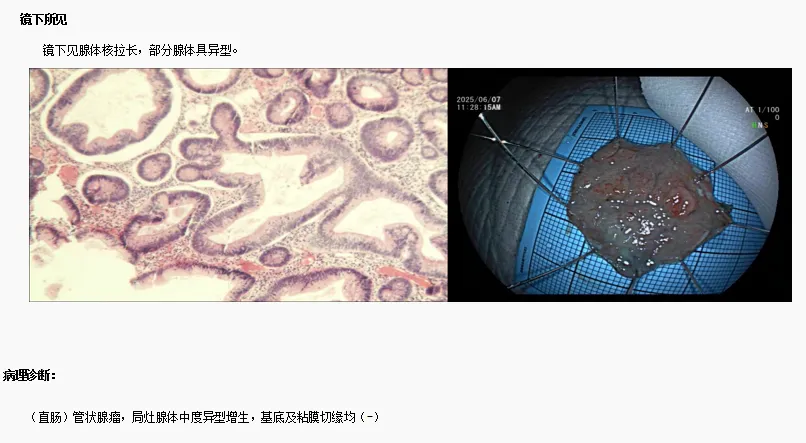

患者胡某,女(nǚ),61歲,因"反複下腹痛1年餘"於2025年5月30日來院就診。結腸鏡檢查發現直腸粘膜隆起(qǐ)病變(LST),患者辦(bàn)理入住(zhù)腫瘤消化科接受內鏡下(xià)ESD治(zhì)療。經充分術前準備及評估,於6月7日在全身麻醉下實施腸鏡下治療。術中發現病灶呈扁平狀,大小約2.0×3.0 cm,表麵顆粒狀,邊界清晰。完成基底注射後,觀察到明顯的抬舉現象。隨後進行(háng)環周切開,完整剝離病(bìng)灶,創麵采(cǎi)用電凝止血,並對部分創麵使(shǐ)用鈦夾進行夾閉處理。切(qiē)除標本(běn)已送(sòng)病(bìng)理檢查。

該病例的成功治療充分體現了內鏡黏膜下剝離術(ESD)在消化道(dào)腫瘤治療中的(de)顯著優勢。通過這項技術,不僅實(shí)現(xiàn)了腫瘤的完整切除,還最大限度地保留了患者的正常(cháng)組織結構和(hé)功能,顯著提升了治療效果和患者(zhě)的生活質量。武寧縣總醫院人(rén)民醫院院區(qū)腫瘤消(xiāo)化科已熟(shú)練掌握內鏡黏(nián)膜(mó)下剝離術(ESD)並常態化開展,憑借(jiè)豐富的臨床經驗和精湛的技術水平,在消化道腫瘤的(de)微創治(zhì)療領(lǐng)域取(qǔ)得了(le)顯著成效,為患者提供精準、安全的治療(liáo)方案,獲得了患者的一致好評(píng)。